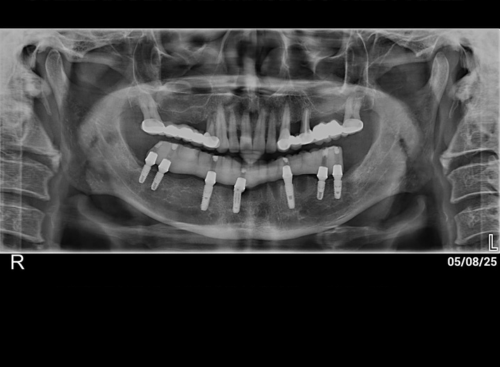

Dental implants are the Benchmark for modern-era tooth replacement, since they merge with your bone. Dental implants become a part of your smile by fixing damaged, or missing teeth with biocompatible screw-like devices mounted with crowns, bridges, and dentures to restore the missing teeth.

The implant teeth are devoid of risks or challenges associated with other dental restoration appliances used in the earlier days. At the Nova Smile Dental clinic, we have talented implant surgeons They will make sure you leave the clinic with a fresh outlook and restored confidence that will stay for a very long time.